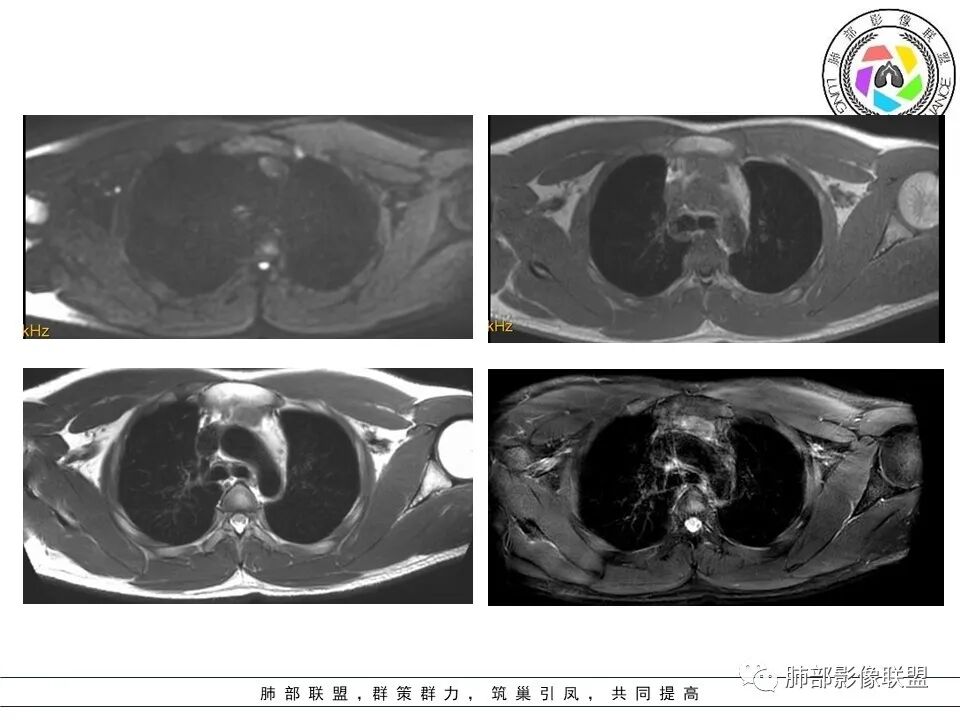

青少年男性,前纵隔结节,多结节间可见脂肪间隙,t2稍高,内见条状低信号,胸腺增生,淋巴瘤,生殖源性肿瘤

3 结节周围有密度稍高的胸腺背景(区别于淋巴瘤) 磁共振正反相位估计有帮助

空格: 部分结节DWI高,T2有积液,不符合胸腺增生,还是淋巴瘤优先考虑。CT增强有环形强化。但DWI病灶中央也亮的,结核可能不大。

DWI好像中央高一些

看这个图

空格: 看到的结节其实还是增生结节,为什么t2有积液,是伴发了脓肿、感染

必有路: 还有坏死区域部分弥散受限

常规会考虑到tb  其他的炎症,还是少见 ,不太优先考虑肿瘤

周边模糊,中央坏死,弥散受限

炎性特点是有的  只是常规会考虑tb  至于化脓性淋巴结炎,症状太轻,没常规考虑

有多发结节,强化不明显,应该周围是增生的胸腺,结节是胸腺囊肿。原因因为里面有炎症细胞,是某种炎症刺激,哪一中炎症细胞?是中性粒细胞还是淋巴细胞?可能并不是感染,而是非感染的炎症刺激了滤泡增生,囊肿形成和纤维修复